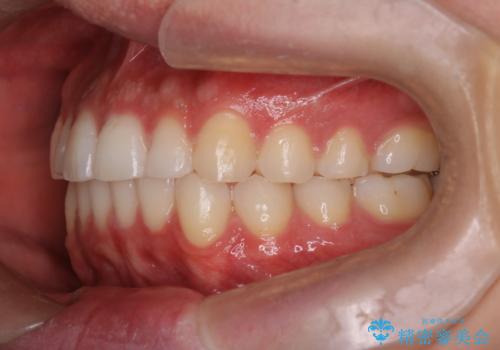

- 前歯の歯並びの改善を希望され来院された患者様です。

初診時の歯並びの状態としては、上下ともに前歯部の中等度以上のがたつき(叢生)があり、右の前歯が1本飛び出した状態でした。

抜歯は行わず上下顎ともに、主に歯列弓の拡大とディスキング(歯と歯の間に隙間を作る処置)を行い叢生を改善しました。

見た目、嚙み合わせ及び、治療期間や施術内容に大変ご満足いただきました。